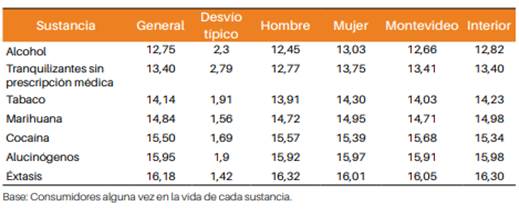

La edad promedio de inicio de consumo varía con el sexo, la sustancia y el ámbito de residencia (Montevideo e interior) (tabla 1) 14.

Tabla 1: edad inicio promedio por sustancia según sexo y ámbito de residencia. Estudiantes de Enseñanza Media. Encuesta Uruguay 2016 (%) 14